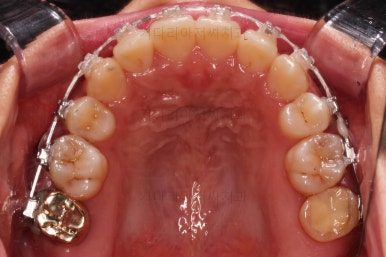

윗니만 추가적으로 발치를 1개 더 했어요.

아랫니는 최대한 추가 발치 없이 후방의 송곳니를 당겨와서 앞니 역할을 하게 했습니다.(총 4개 앞니처럼)

부분적으로 장치 셋팅을 다시 해줬고요.